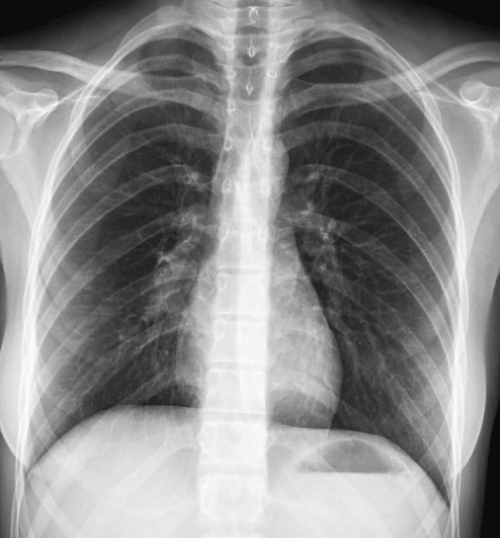

In her past medical history she had hypothyroidism and epilepsy. Laboratory tests revealed iron deficiency anemia whereas other biochemical tests were normal. In posteroanterior chest radiogram a fine bordered solid lesion with 7 cm diameter was observed in right paracardiac area having continuity with right hilar region (Figure 1). Thorax Computerized Tomography (CT) performed at another center revealed; several lymph nodes with diameter of 9-10 mm in bilateral axillary regions, 6 × 6 cm soft tissue density obliterating right lower lobe bronchus and indented to main bronchus in right hilar region, 3 × 2 cm soft tissue density with irregular borders in right lower lobe (Figure 2). In Positron Emission Tomography (PET) CT examination, 6 × 5.5 cm hypermetabolic (SUV max 23) lesion having lobular contours and invasion to mediastinum was detected in right hilar region (Figure 3).

Figure 1: Image from pre-diagnosis chest x-ray. View Figure 1

Lesions observed in chest radiogram are most important radiologic sign in our patient. Chest radiogram of our patient revealed; fine bordered 7 cm in size paracardiac mass having continuity with right hilar region (Figure 1). Thoracic tomography should be performed in young patients with hemoptysis and if necessary bronchoscopy should not be avoided. These methods can provide more information about the characterization of the lesion in the lung. Primary pulmonary lymphoma is a presentation of less than 1% of lung cancers, and less than 1% of malignant lymphomas [5]. The most common primary lymphoma of the lung is low-grade Mucosa Associated Lymphoid Tissue (MALT) lymphoma arising from the bronchus and the second is diffuse large B-cell lymphoma.